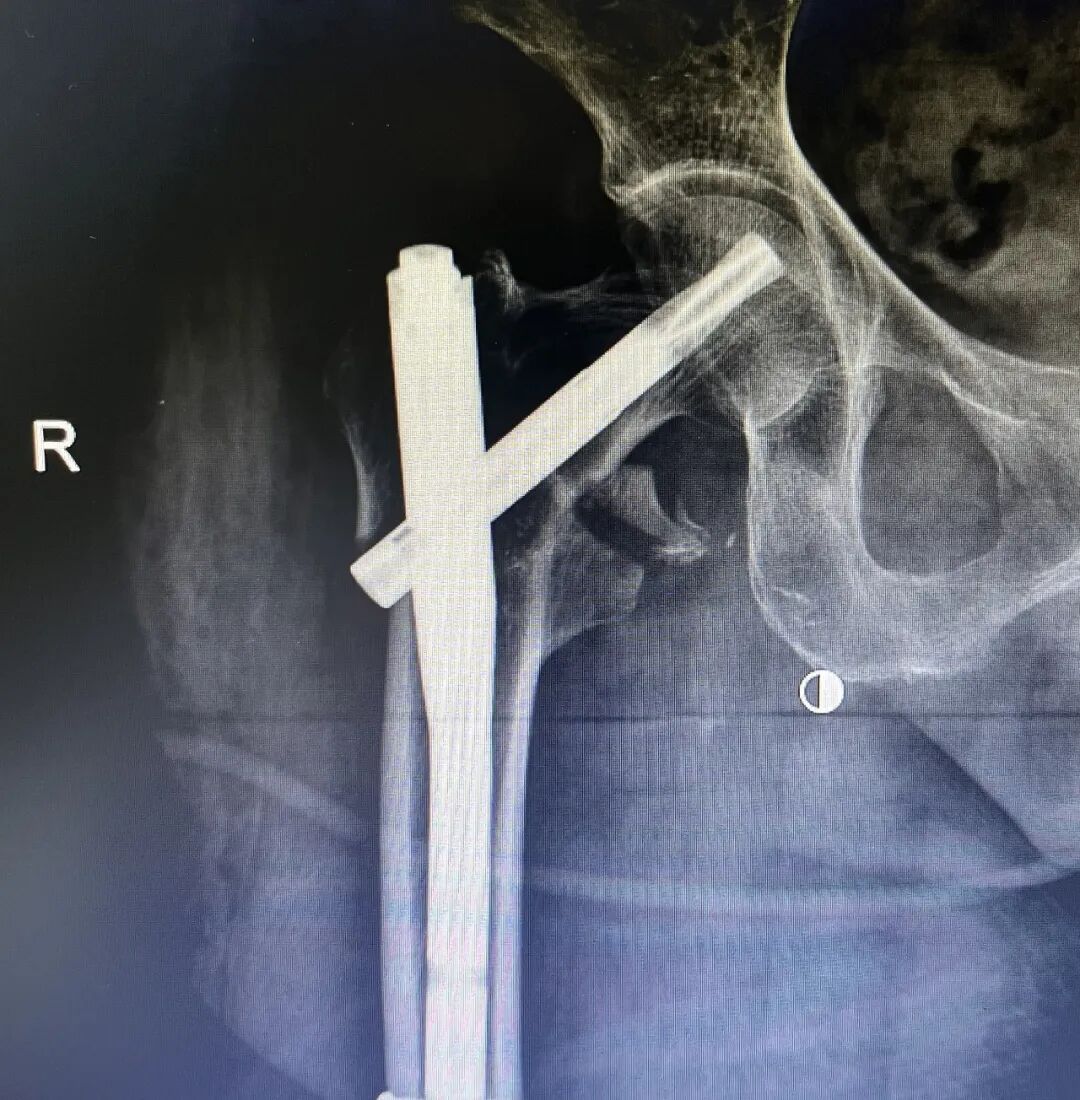

近日,我科收住一位高齡患者,孫某某,女,82歲,患者2小時(shí)前因摔傷致全身多處腫痛、伴活動(dòng)受限。入院后診斷:1.右股骨粗隆間粉碎性骨折;2.右尺橈骨遠(yuǎn)端粉碎性骨折;3.右鎖骨骨骨折;4.右肱骨大結(jié)節(jié)骨折;5.右恥骨下肢骨折;6.重度骨質(zhì)疏松。 鑒于患者屬高齡,損傷重,病情復(fù)雜,入科后科主任魏國(guó)華帶領(lǐng)關(guān)節(jié)骨科醫(yī)護(hù)團(tuán)隊(duì)積極完善相關(guān)檢查、科學(xué)制定治療方案,充分發(fā)揮中醫(yī)骨傷的治療優(yōu)勢(shì),保守與手術(shù)相結(jié)合,對(duì)右尺橈骨遠(yuǎn)端粉碎性骨折行手法復(fù)位石膏托外固定術(shù)。 排除手術(shù)禁忌后,在腰硬聯(lián)合麻醉下行右股骨粗隆間粉碎性骨折閉合復(fù)位PFNA內(nèi)固定術(shù),其余疾病行保守治療,術(shù)后經(jīng)活血化瘀、益氣養(yǎng)血等積極對(duì)癥治療,患者肢體功能恢復(fù)良好,已康復(fù)出院。 股骨粗隆間骨折是老年人常見(jiàn)損傷,俗稱人生最后一次骨折。老年人骨質(zhì)疏松,肢體不靈活,當(dāng)下肢突然扭轉(zhuǎn)、跌倒或使大粗隆直接觸地?fù)p傷,甚易造成骨折。由于粗隆部受到內(nèi)翻及向前成角的復(fù)合應(yīng)力,引起髖內(nèi)翻畸形和以小粗隆支點(diǎn)的嵌壓形成小粗隆蝶形骨折。亦可由髂腰肌突然收縮造成小粗隆撕脫骨折。粗隆部骨質(zhì)疏松脆,故骨折常為粉碎型。 就診地址:酒泉市中醫(yī)醫(yī)院關(guān)節(jié)骨科?? ?? 門診部:二樓205診室 住院部:綜合樓6樓住院部